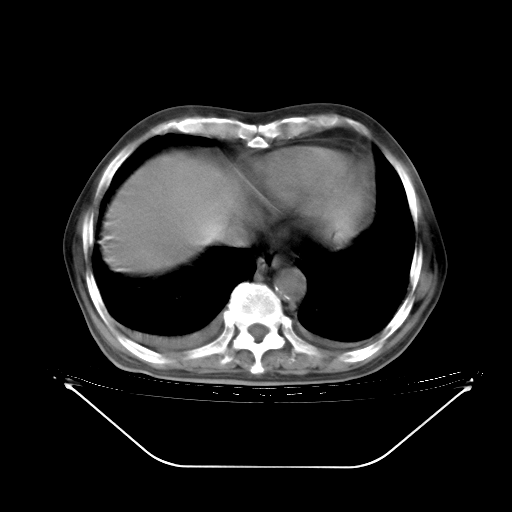

今天复查肺部CT,发现双肺广泛磨玻璃样改变。所以我把3月19日和5月9日相隔50天的肺部CT上传。请大家会诊。

2009年3月19日肺部CT片。

5月9日肺部CT(在4月27日齐鲁医院肺部CT描述部分肺组织磨玻璃样改变,12天后肺组织广泛磨玻璃样改变)